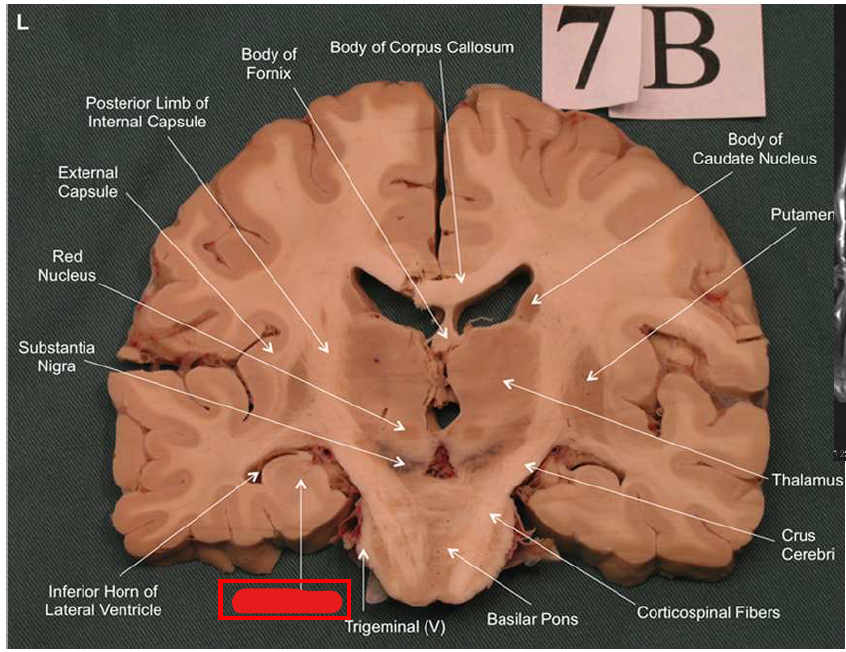

What structure has the function of reducing unpleasant effects of stress, psychological resistance, and formation of new memories?

hippocampus

What is the fornix of the hippocampus?

Hippocampus output pathway (C-shaped)

Connects hippocampus to hypothalamus/mamillary bodies

Carries information to and from hippocampus

Important for memory consolidation and retrieval

What is this?

hippocampal fornix

How does the hippocampus form memories?

Association areas activate the hippocampus, which reverberates in the Papez circuit until information is stored permanently

Hippocampus → fornix → mamillary bodies → anterior thalamic nucleus → cingulate cortex → hypothalamus

What is Korsakoff syndrome?

Memory disorder from thiamine (vitamin B1) deficiency. Often linked to chronic alcoholism.

Symptoms: anterograde amnesia (can't form new memories), confabulation (making up memories), disorientation, apathy.